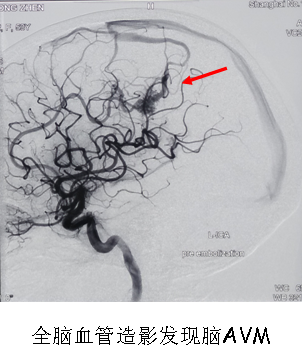

我院成功开展全脑血管造影手术

9月8日下午,我院DSA手术室正在紧张地为二名脑出血患者行全脑血管造影手术,无影灯下手术医生与护士配合默契,“加压滴注、排气、穿刺动脉、置导管鞘、推造影剂、减影……”一系列手术操作有条不紊地进行着。

患者王某,女性,54岁,因左侧顶枕叶脑出血收住入院,既往无高血压病史,病情稳定后经DSA检查现已明确为左侧顶叶脑动脉静脉畸形;另一患者肖某,女性,74岁,因自发性蛛网膜下腔出血收住入院,经本次手术检查已明确为右侧大脑后动脉动脉瘤。两名患者通过本次手术均很快找到出血病因,为后续治疗指明方向及制定治疗方案提供了可靠依据。

这两台手术的顺利完成,标志着我院神经外科在脑血管疾病的诊断及诊治方面进入了一个新的阶段,同时也是大丰地区该项新技术零的突破,再一次显示了我院整体医疗实力的显著提高。我院也将不断创新,大力开展新技术、新项目,更好地为大丰人民提供优质的医疗服务。